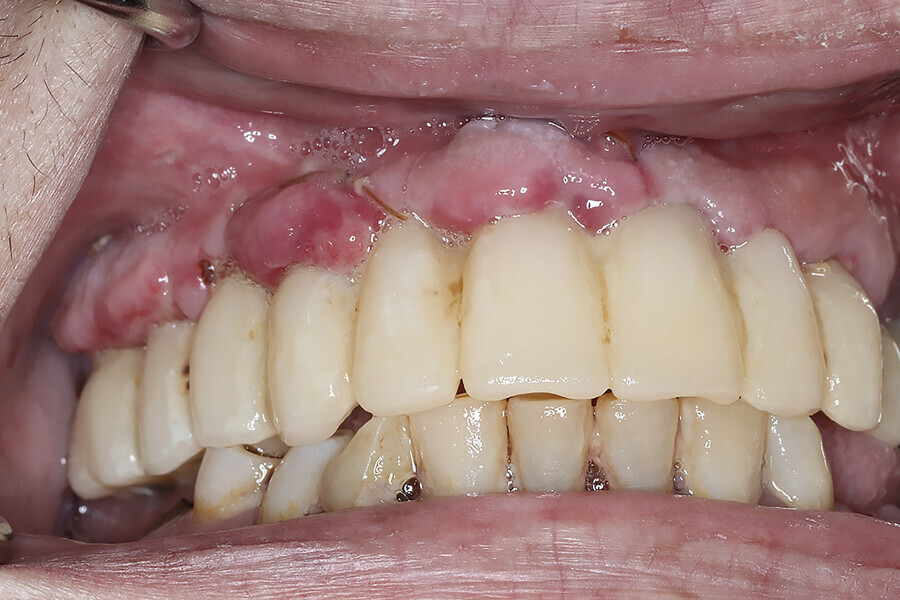

Fig. 11e: Pre-op photograph showing a reverse curve of the mandibular teeth and poor aesthetics.

During the subsequent postoperative visits, the patient described being extremely happy with his newly rehabilitated mouth. As the preliminary provisional restorations had been designed based on the desired virtual result, it was possible to make changes as necessary for the final restorations. A slight discrepancy was observed in initial tooth size and midline position, and this was noted in order to be corrected during finalisation of the monolithic zirconia restorations. The patient tolerated the 2 mm increase in VDO, and minimal adjustments to the occlusion were accomplished through digital articulation (OccluSense, Bausch). Tissue healing was unremarkable apart from minor loss in alveolar height and soft tissue in the impacted canine extraction site.